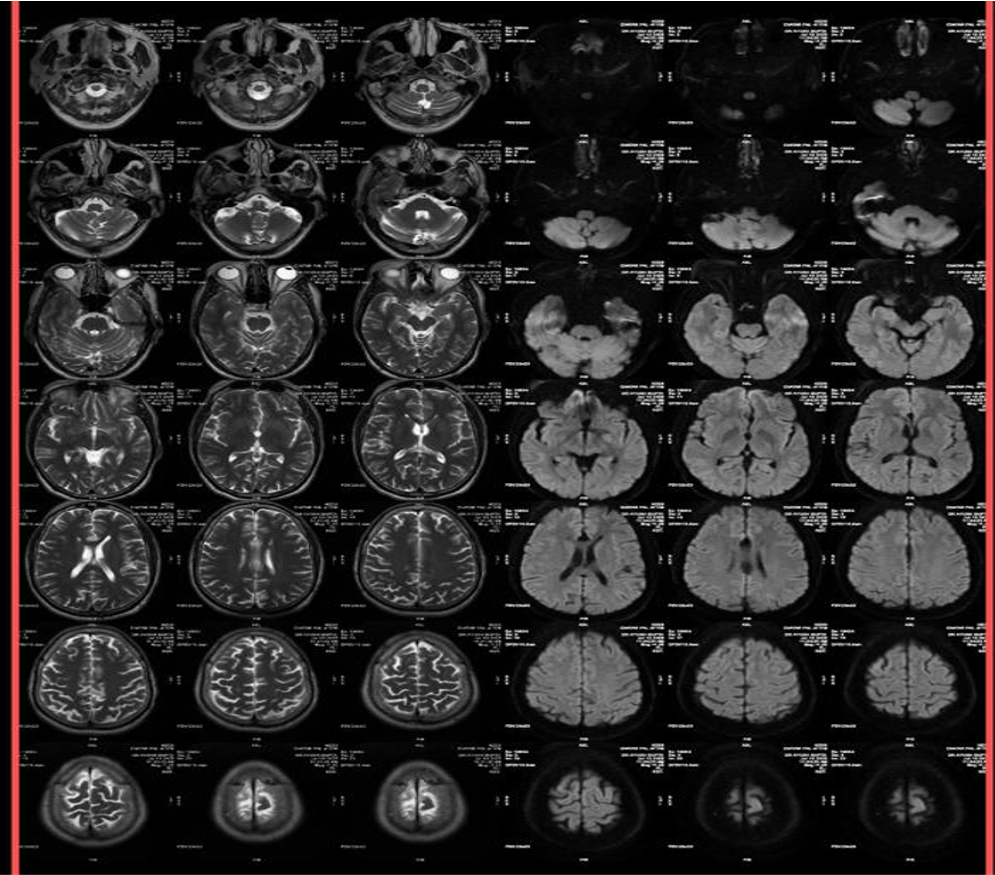

Imaging Findings-

- CT

- Well-defined, homogeneous, hypodense lesion (-50 to -100 HU, consistent with fat).

- May show peripheral or central calcifications (~50% cases).

- No enhancement with contrast.

- MRI

- T1-weighted: Hyperintense (fat signal).

- T2-weighted: Variable, usually hyperintense; may show chemical shift artifacts.

- Fat-suppressed sequences: Complete signal suppression confirms fat composition.

- Post-contrast: No enhancement.

- Often associated with:

- Corpus callosum agenesis/dysgenesis

- Interhemispheric cysts

- Calcifications (better on CT)